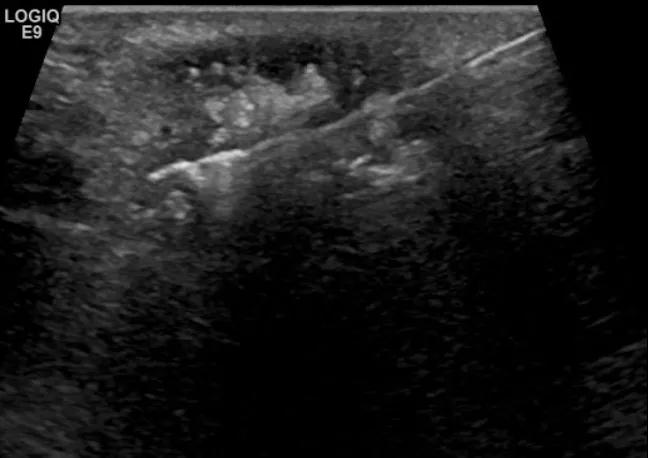

第四例是胸腺癌化妆包,术后、化疗之后淋巴结转移,肿块范围巨大,99mm*61mm,边界不清,呈浸润状,肿块包绕颈动脉,颈内静脉压闭,症状明显。由于患者放化疗也不敏感、血供非常丰富,于是采取多点姑息性消融。姑息性消融后未实现完全消融,病灶大片坏死,肿胀疼痛得到明显的缓解,后续患者未再来复查。

(病例4图例)